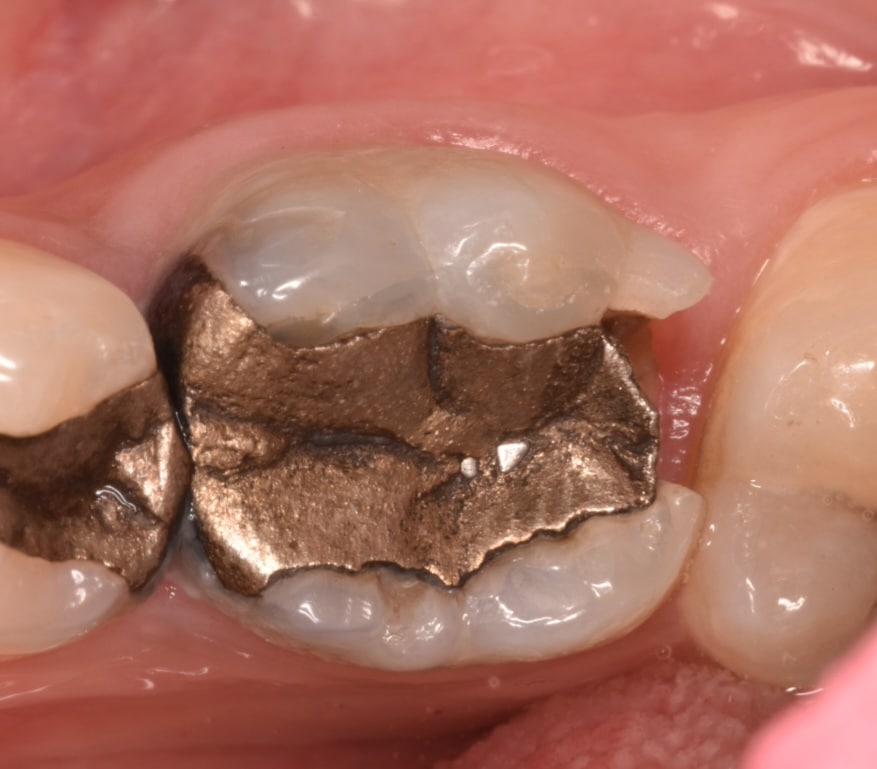

Old amalgam and screw removed

The empty space in the canal treated and filled with dual cure material

IDS with gold standard clearfil SE bond ,

D.M.E and biobase

Biobase ,

The pulpl chamber filled with ever x posterior and coverd by GC composite